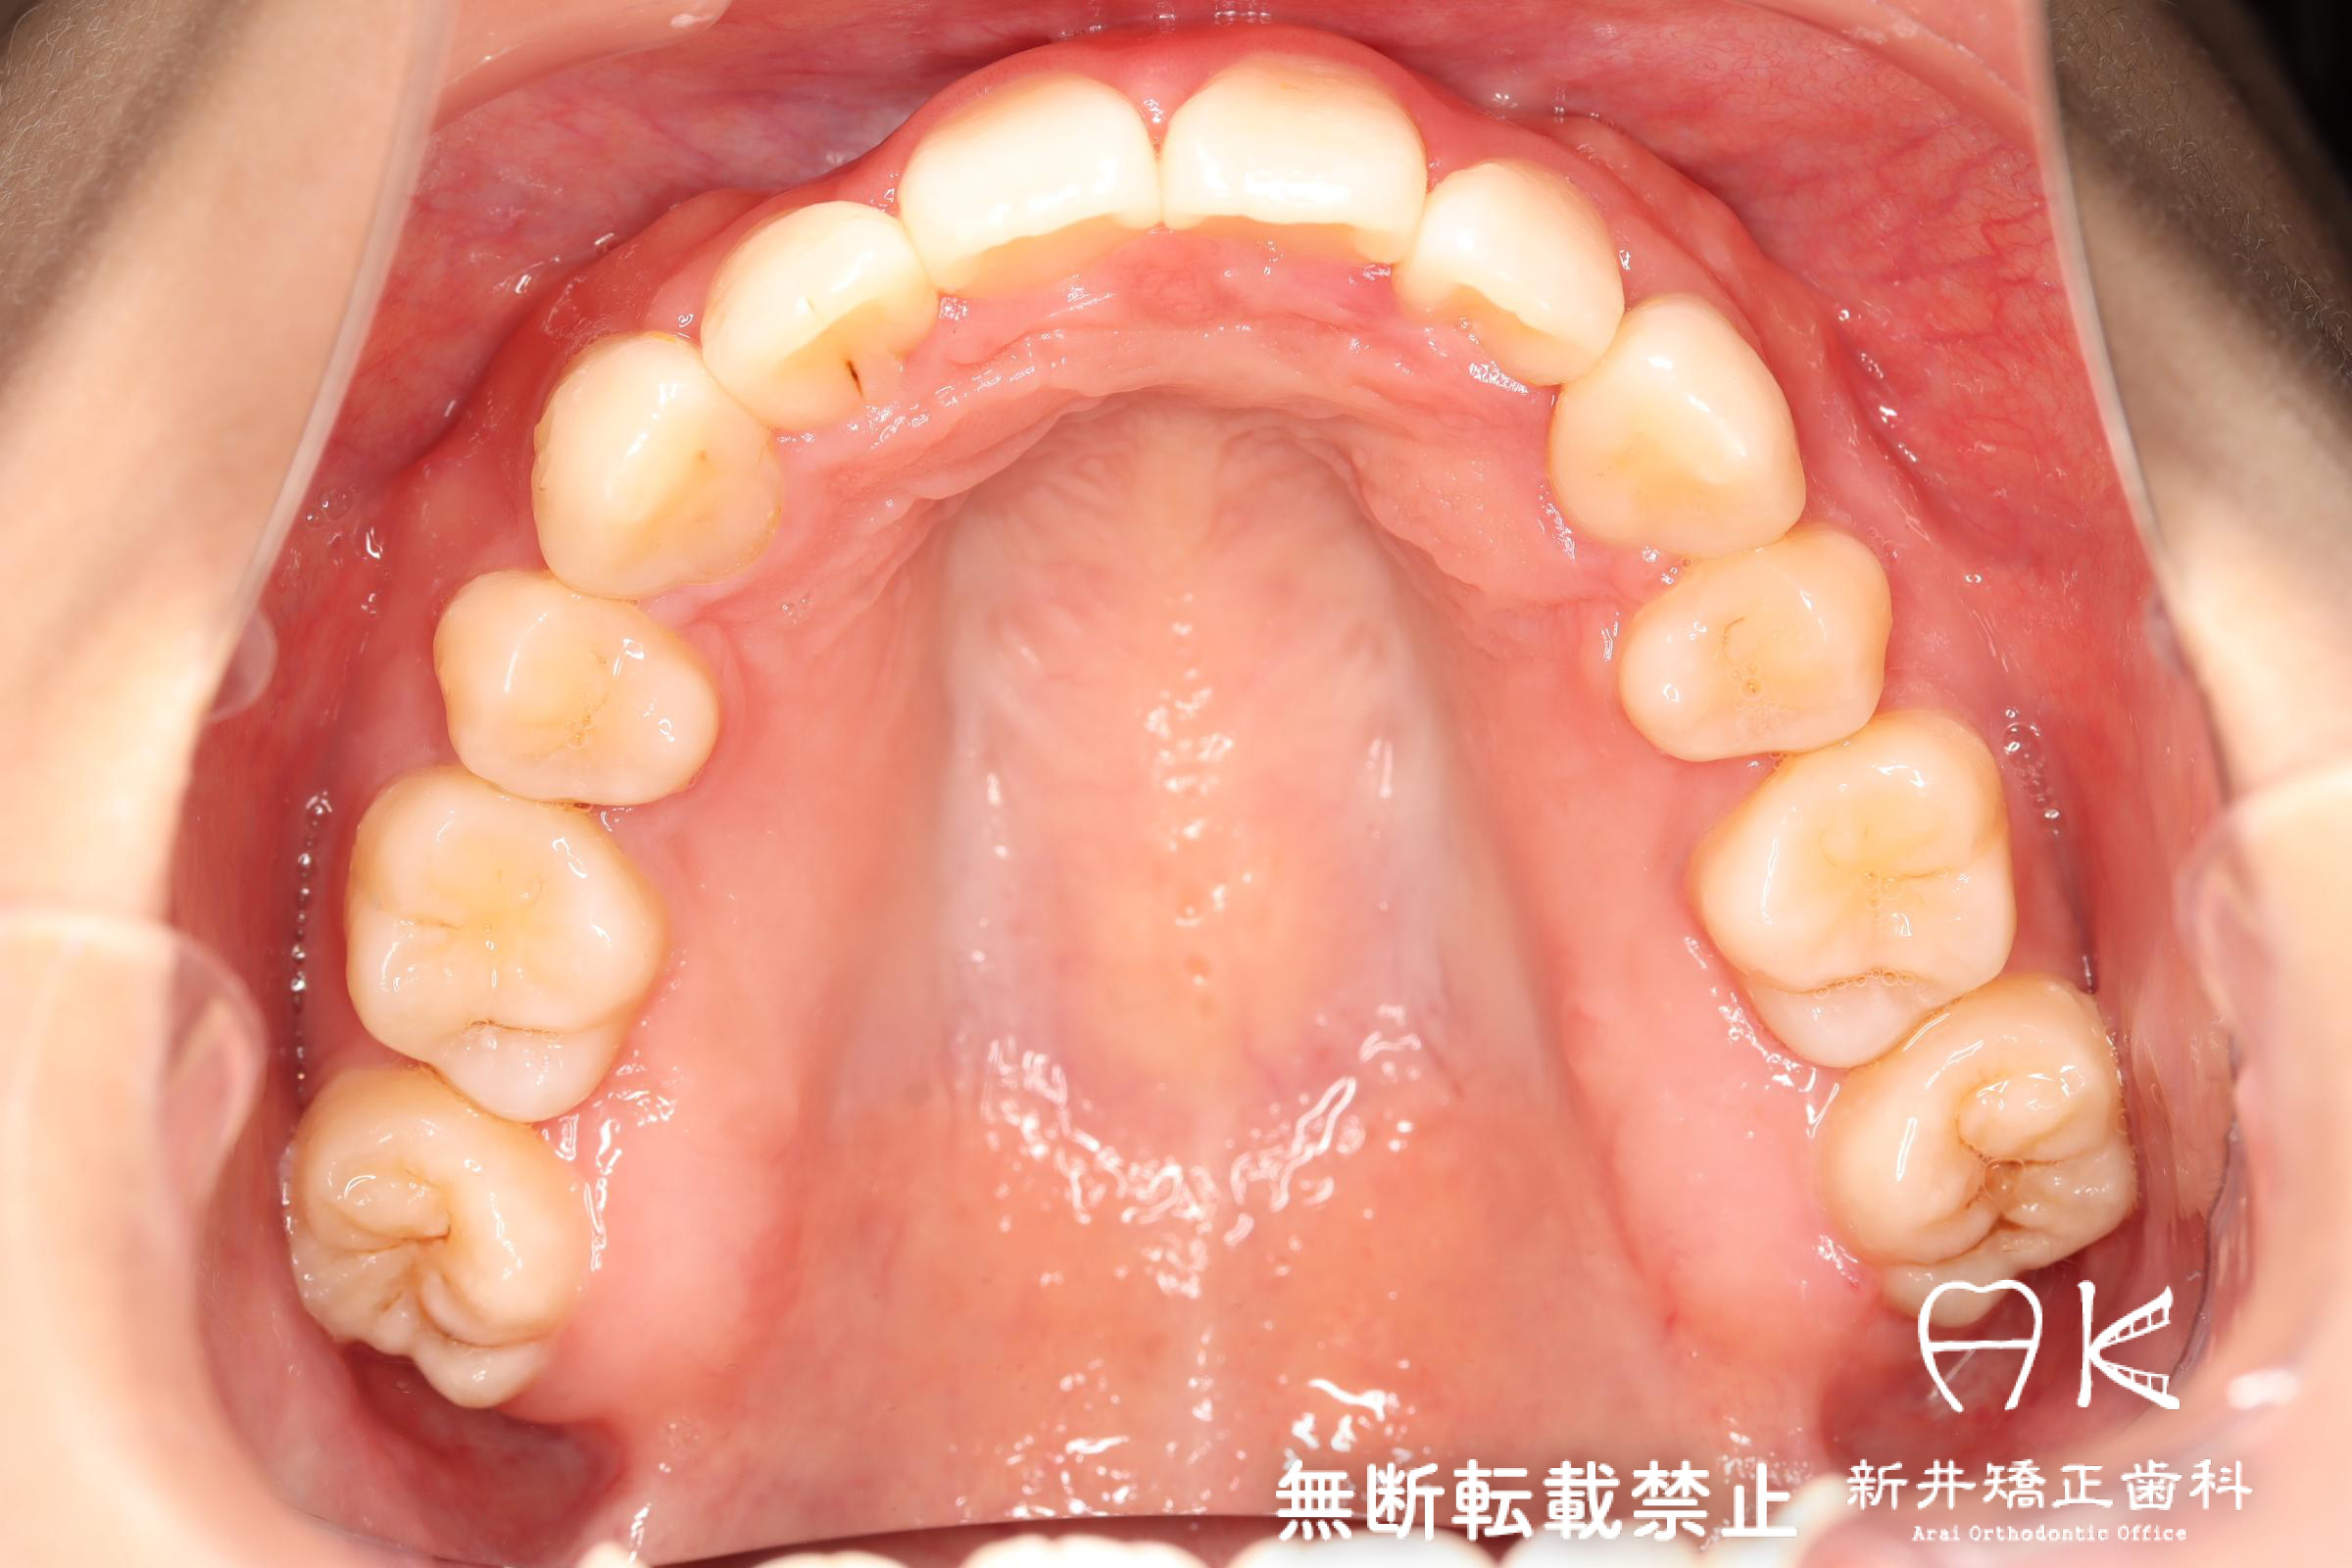

| 治療後 | 前歯から奥歯まで全体的に緊密な咬み合わせになっています。 治療前後のセファログラムのトレースの重ね合わせを比較すると、上下の歯列の後方移動ができ、それにより口元もよりすっきりしました。 また前歯の唇側傾斜も改善されています。 |